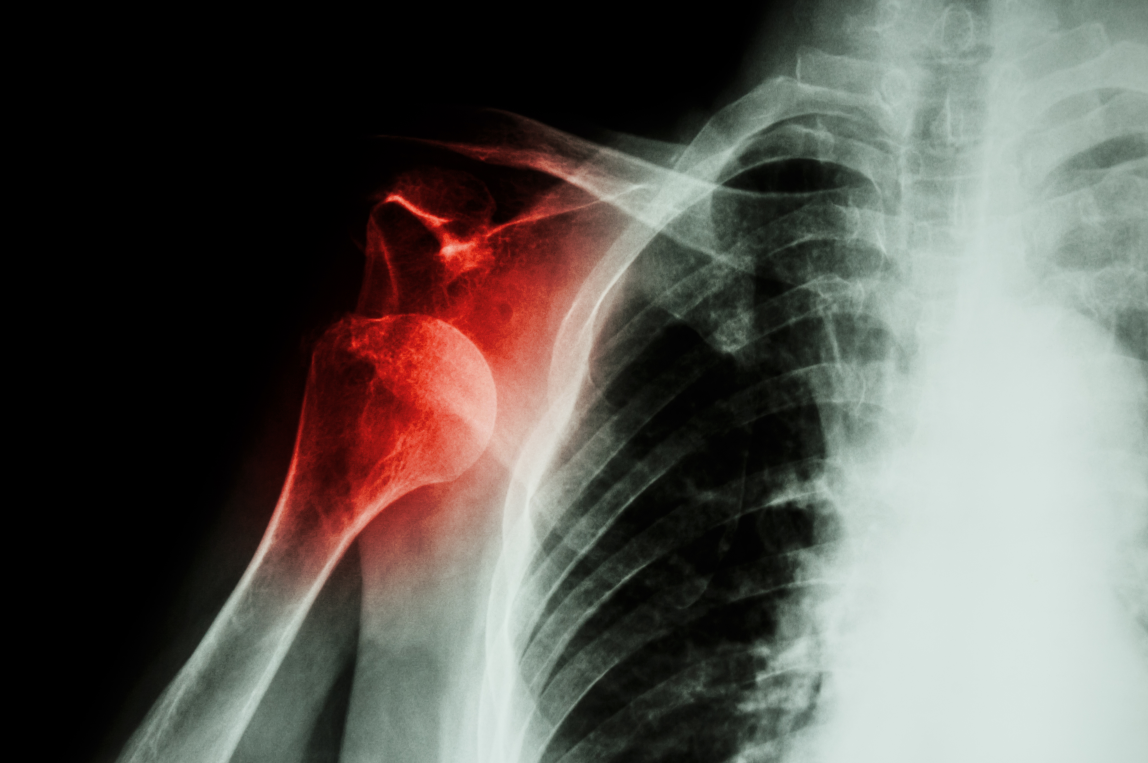

图文结合:遇见肩峰骨折怎么治疗?看看这篇!

肩峰骨折是一种临床非常少见的骨折类型,指肩胛骨外侧与肱骨形成关节突出的部分出现的骨折,多由于直接暴力引起。